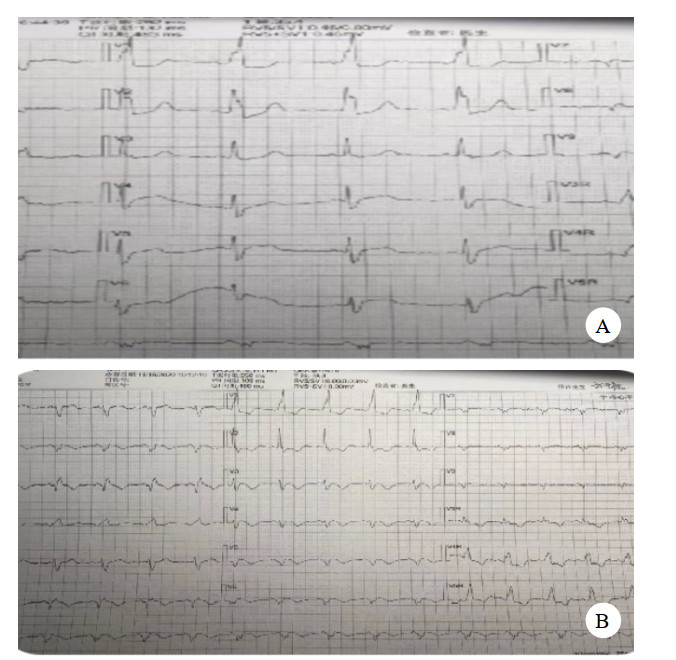

住院期间查肝功能、肾功能、凝血常规、电解质均正常范围;血脂常规:总胆固醇4.5 mmol/L,甘油三酯1.8 mmol/L,低密度脂蛋白2.2 mmol/L,HDL 1.2 mmol/L;血管炎、抗核抗体谱正常范围;免疫全套:总IgE 1959 IU/ mL;复查心电图见图 4。

| 图 4 患者术后复查心电图 |

复查心脏彩超:左房(LA 35 mm)左室稍大(LV 52 mm);左室下壁及后侧壁室壁稍变薄并运动减弱;二尖瓣、三尖瓣、主动脉瓣轻度反流,左室收缩及束支功能减退(EF:39%)。

患者总IgE明显升高,而IgE与I型变态反应有关,过敏体质或超敏患者,血清中IgE明显高于健康者。结合患者冠脉造影检查,考虑患者血管痉挛可能由过敏反应导致。于是在原治疗方案基础上加用糖皮质激素(使用3 d) 及地氯雷他定,经调整治疗后患者心衰症状逐渐平稳,住院期间未在出现冠脉痉挛相关症状。